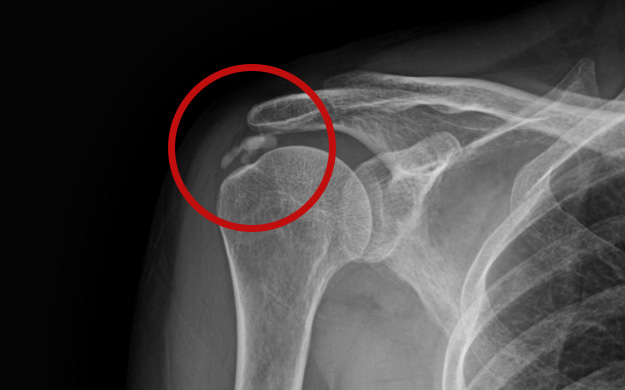

어깨 힘줄 내부에 칼슘 석회가 침착되어 힘줄의 손상과 함께 통증을 유발하는 질환입니다.

석회화건염은 외상으로 인해서 발생하는 것과 무관합니다.

어깨 속에 석회가루가 쌓여 통증을 유발하는 석회화건염은

움직임이 제한되고 혈액순환 장애와 염증반응을 유발합니다.

석회는 신체 어느 부위에서나 발생할 수 있으나 어깨에 가장 많이 발생합니다.